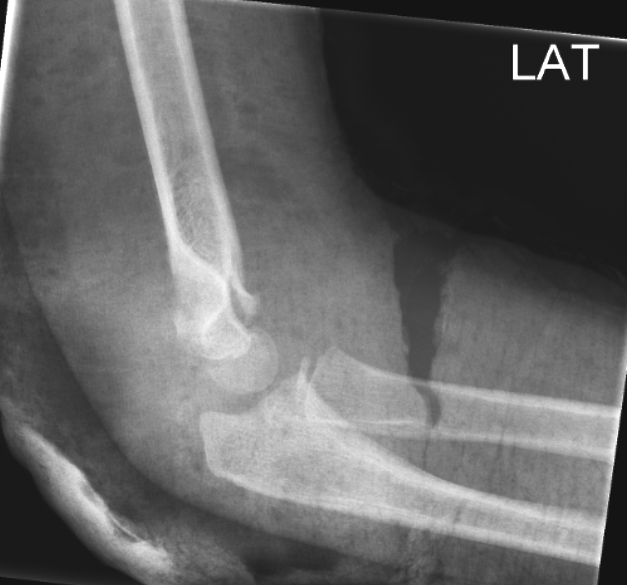

BOWING ULNA:

Normal:

Bemærk dislocation af radius. Skal reponeres i GA.